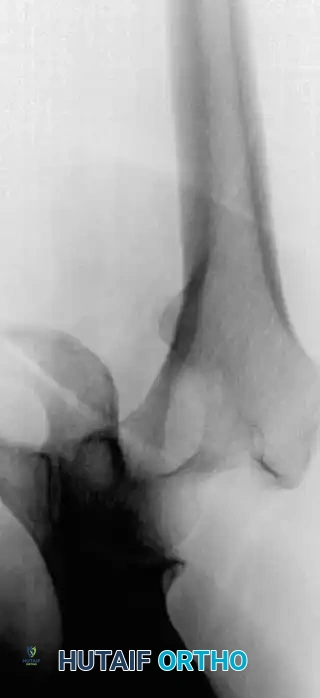

Fig. 22-19: (A) Anteroposterior view of the left hip of a 50-year-old woman with a history of breast cancer, disease-free for 2 years. A lytic lesion is seen in the femoral neck. Although the most likely diagnosis is metastatic carcinoma, a biopsy must be performed. This lesion proved to be a malignant fibrous histiocytoma (primary sarcoma). (B) Anteroposterior view after wide resection and endoprosthetic reconstruction. Prophylactic fixation of this presumed metastasis would have severely compromised her oncologic outcome.